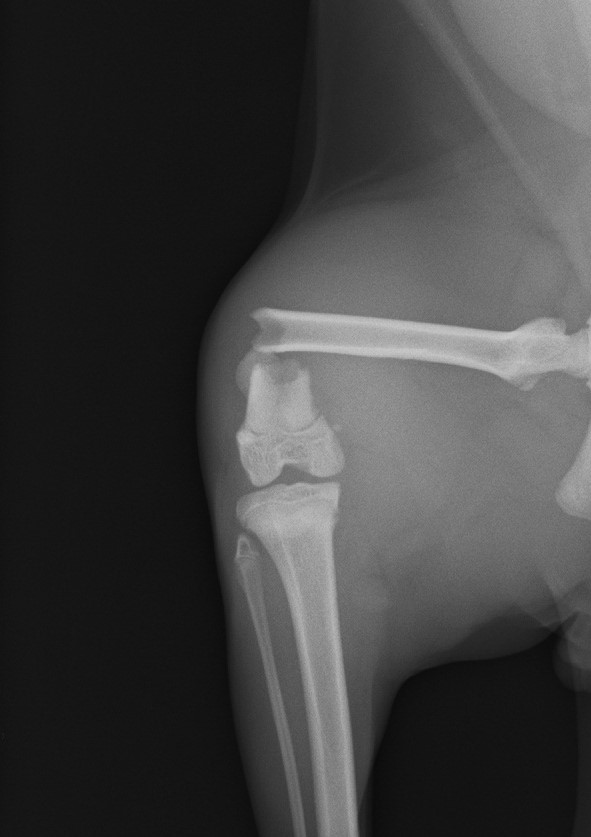

骨端部骨幹端骨折(術前)

高所からの落下など骨端部骨折は少なくありません。端の手術のため難易度が高くなります。